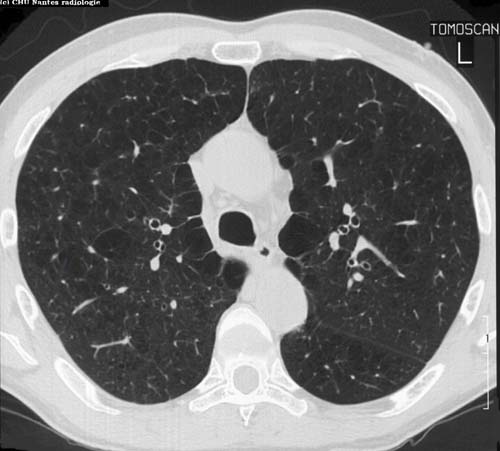

Emphysème pulmonaire débutant